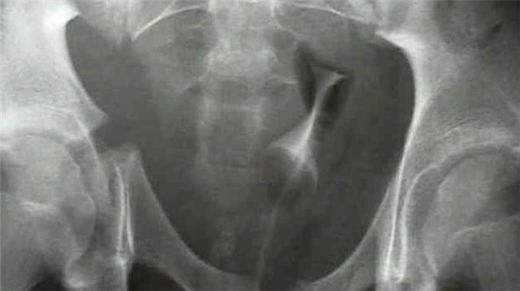

Pelvis Kemiği Önemi